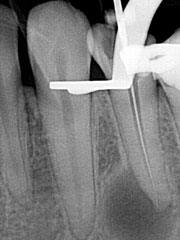

Конечная цель врача при эндолечении – расширить, отмыть и запломбировать канал зуба на всю длину, ровно до верхушки. При этом плохо, если есть «перелет» или «недолет». Как правильно определить точную длину канала и почему это важно? «Перелет» или попадание пломбировочного материала за верхушку зуба в окружающую кость нежелательно, т.к. может привести к различным осложнениям. «Недолет», запломбированный не до верхушки зуб чаще всего приводит к возникновению гранулем и кист, т.к. остается необработанная зона, в которой поселяется «плохая» микрофлора. Как же точно определить длину канала? Для этого врач стоматолог пользуется рентгеном и/или (лучше безусловно «и») апекслокатором. С рентгеном я думаю все понятно, многие с ним сталкивались. Стоматолог вводит в канал инструмент, отмечает на нем длину и делает снимок. После этого он может эту длину объективно откорректировать. Апекслокатор – очень удобный прибор, этакий эндодонтический парктроник. Он подключается к инструменту, которым доктор расширяет канал, и при приближении кончика инструмента к верхушке корня начинает пищать, чем ближе, тем интенсивнее… точь-в-точь как парктроник в автомобиле. Таким образом стоматолог может в реальном времени контролировать глубину погружения инструмента с точностью до долей миллиметра. Причем первые апекслокаторы достаточно сильно врали, особенно если канал не был сухой… Современные приборы дают очень точные результаты, практически сведя к минимуму необходимость постоянного обращения к рентгену. При этом все же золотой стандарт эндодонтии – использование апекслокатора на протяжении всего лечения, плюс 3 рентгеновских снимка для каждого зуба: статус до лечения, во время (как правило, с инструментами или штифтами, погруженными на всю длину всех каналов), после окончания лечения каналов и реставрации зуба. Причем роль этих снимков скорее документальная.

На этом рентгеновском снимке видны, в первую очередь, «пустые» корневые каналы и довольно больших размеров очаг воспаления (то, что часто называют гранулемой, кистой) на верхушке одного из корней. В общем итоге в одном зубе был сконцентрирован целый букет ошибок и недоделок, одним словом, это образец недобросовестной работы стоматолога. Я стараюсь о коллегах всегда говорить или хорошо или молчать, но в данном случае надо смотреть правде в глаза – зуб загублен именно стоматологом. Никаких объективных сложностей для качественной работы изначально здесь не было. Зато появились теперь. Прогноз на будущее для таких зубов всегда строится, исходя из 2 основных проблем – насколько приведет к успеху повторное лечение каналов и насколько будет успешной попытка адекватного восстановления зуба после этого. Оценив вероятность долговременного успеха этих двух составляющих, можно решать, стоит ли «спасать» зуб от щипцов хирурга. Ведь, в любом случае, лечение стоит денег, а гарантировать результат здесь невозможно. Можно только предполагать вероятность успеха. В данном случае каналы не выглядели непроходимыми. Да и восстановить зуб коронкой, даже несмотря на большую степень разрушения, все еще представлялось возможным. А потому было принято решение о начале лечения.